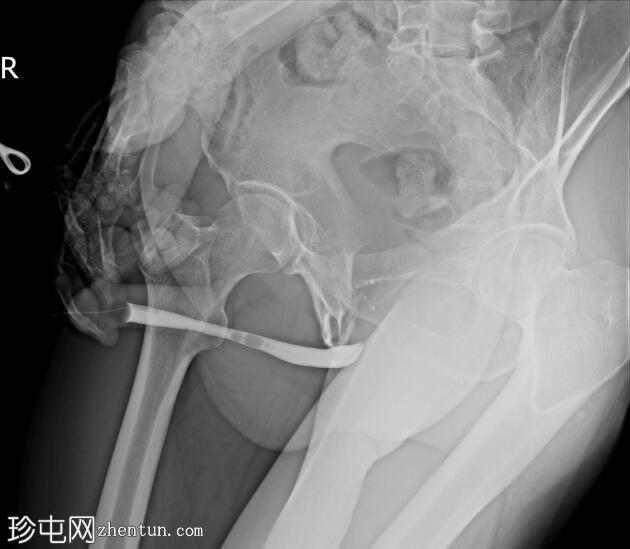

正位

斜位

前列腺部、膜部、球部及阴茎部尿道均正常。

造影剂经尿道注入,开始充盈具有肠袢特征的新膀胱。

该患者确诊为移行细胞癌后行膀胱切除术。治疗方案包括根治性膀胱切除术及新膀胱重建术。